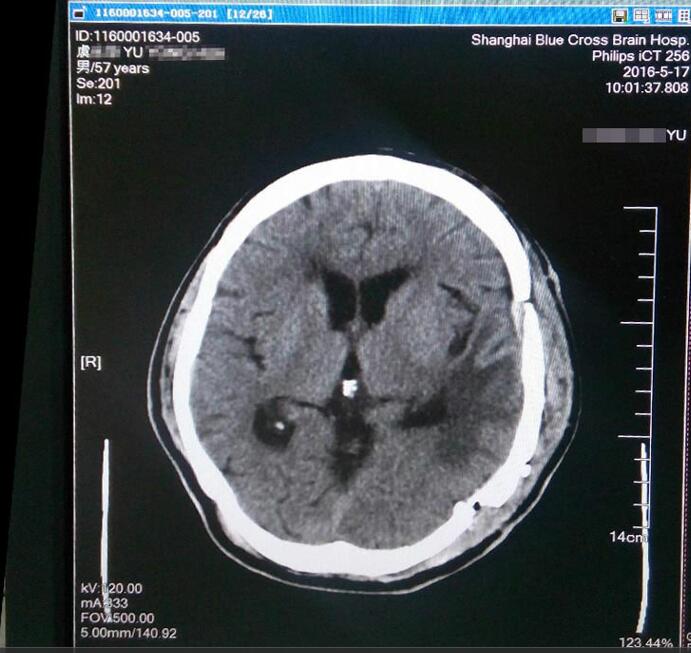

虞文军这才意识到问题的严重性,至当地医院就诊,行头颅CT检查示:左侧颞区底部大脑凸面可见类圆形略高密度占位病变,周围见低密度水肿影,CT值为44HU,大小约为8*6cm,周边脑组织及脑室受压,中线结构右移,额顶部软组织肿胀,考虑为左侧底部脑膜瘤。为求进一步治疗,经过四处打听,虞文军在爱人的陪同下于2016年4月22日前来上海蓝十字脑科医院就诊。

术前检查肿瘤清晰可见

患者入院后行头颅MR+增强及MRA发现:肿瘤供血丰富,供血起源于小脑幕上动脉。经包括沈建康教授在内的专家会诊后,考虑到患者脑肿瘤巨大(8*6cm)、肿瘤周边血供丰富,手术指征明确,常规手术切除恐出血过多,增加手术风险,决定术前先为虞文军行“超选择性全脑血管造影术+脑膜瘤供血动脉栓塞术”,对肿瘤供血动脉进行栓塞,减少出血量,再全麻下行“左侧颞底部巨大脑膜瘤切除术”。 沈建康教授表示:“ 我10年都没见过这么大的脑肿瘤了”。 患者术后随即恢复清醒,自我感觉头脑较前更清醒,语音、语速恢复较好,不到半个月便已能正常行走,顺利出院。